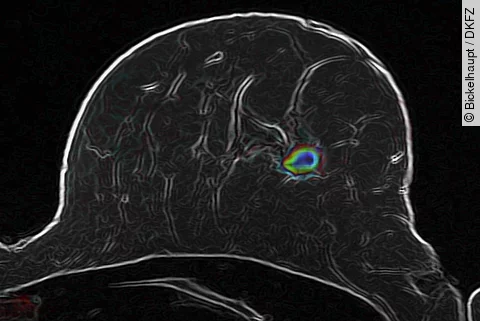

Die Diagnostik von Brustkrebs zu verbessern ist das erklärte Ziel eines Forscherteams vom Deutschen Krebsforschungszentrum in Heidelberg. Die Wissenschaftler kombinieren eine Weiterentwicklung der diffusionsgewichteten Magnetresonanztomografie mit intelligenten Bildanalyseverfahren, um bösartige Veränderungen im Gewebe aufzuspüren. Diese Methode könnte künftig viele Kontrollbiopsien nach einem auffälligen Mammographie-Befund ersparen.